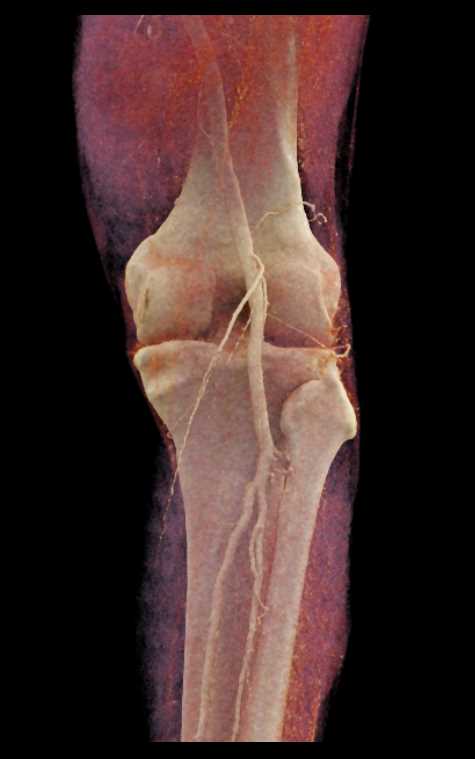

GSW with Bleed Near Knee